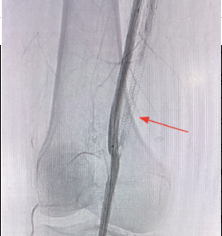

The Endocross was then removed, and a 5 mm PTA balloon was advanced over the Choice PT .014-inch wire across the distal venous and arterial anastomoses. The PTA balloon was used for the dilatation of the distal arteriovenous anastomosis. The PTA balloon was then advanced and the Choice PT .014-inch wire was exchanged for a Supra Core 300 cm wire (Abbott). The first stent graft was placed, extending a minimum of 3 mm into the distal popliteal artery. Three overlapping stent grafts were deployed, extending from the popliteal artery to the proximal SFA, followed by post-dilation extending approximately 2 mm above the proximal edge of the SFA and profunda bifurcation. The stent delivery system was removed. The graft was then post dilated with a 6 mm PTA balloon focusing on the anastomosis. A final angiogram procedure was performed to visualize anterior artery blood flow in the anterior tibial artery. A final venogram was performed and venous flow was visualized. An Angio-Seal (Terumo) was used to close the left femoral artery. Final imaging demonstrated an open percutaneous femoral popliteal bypass (Figure 3, Video). The patient was discharged on Eliquis 2.5 mg with plans for repeat arterial Doppler at one month, 3 months, 6 months, and thereafter in a yearly fashion. At the one-month follow-up, the bypass was found to be widely patent and the patient remained symptom free.